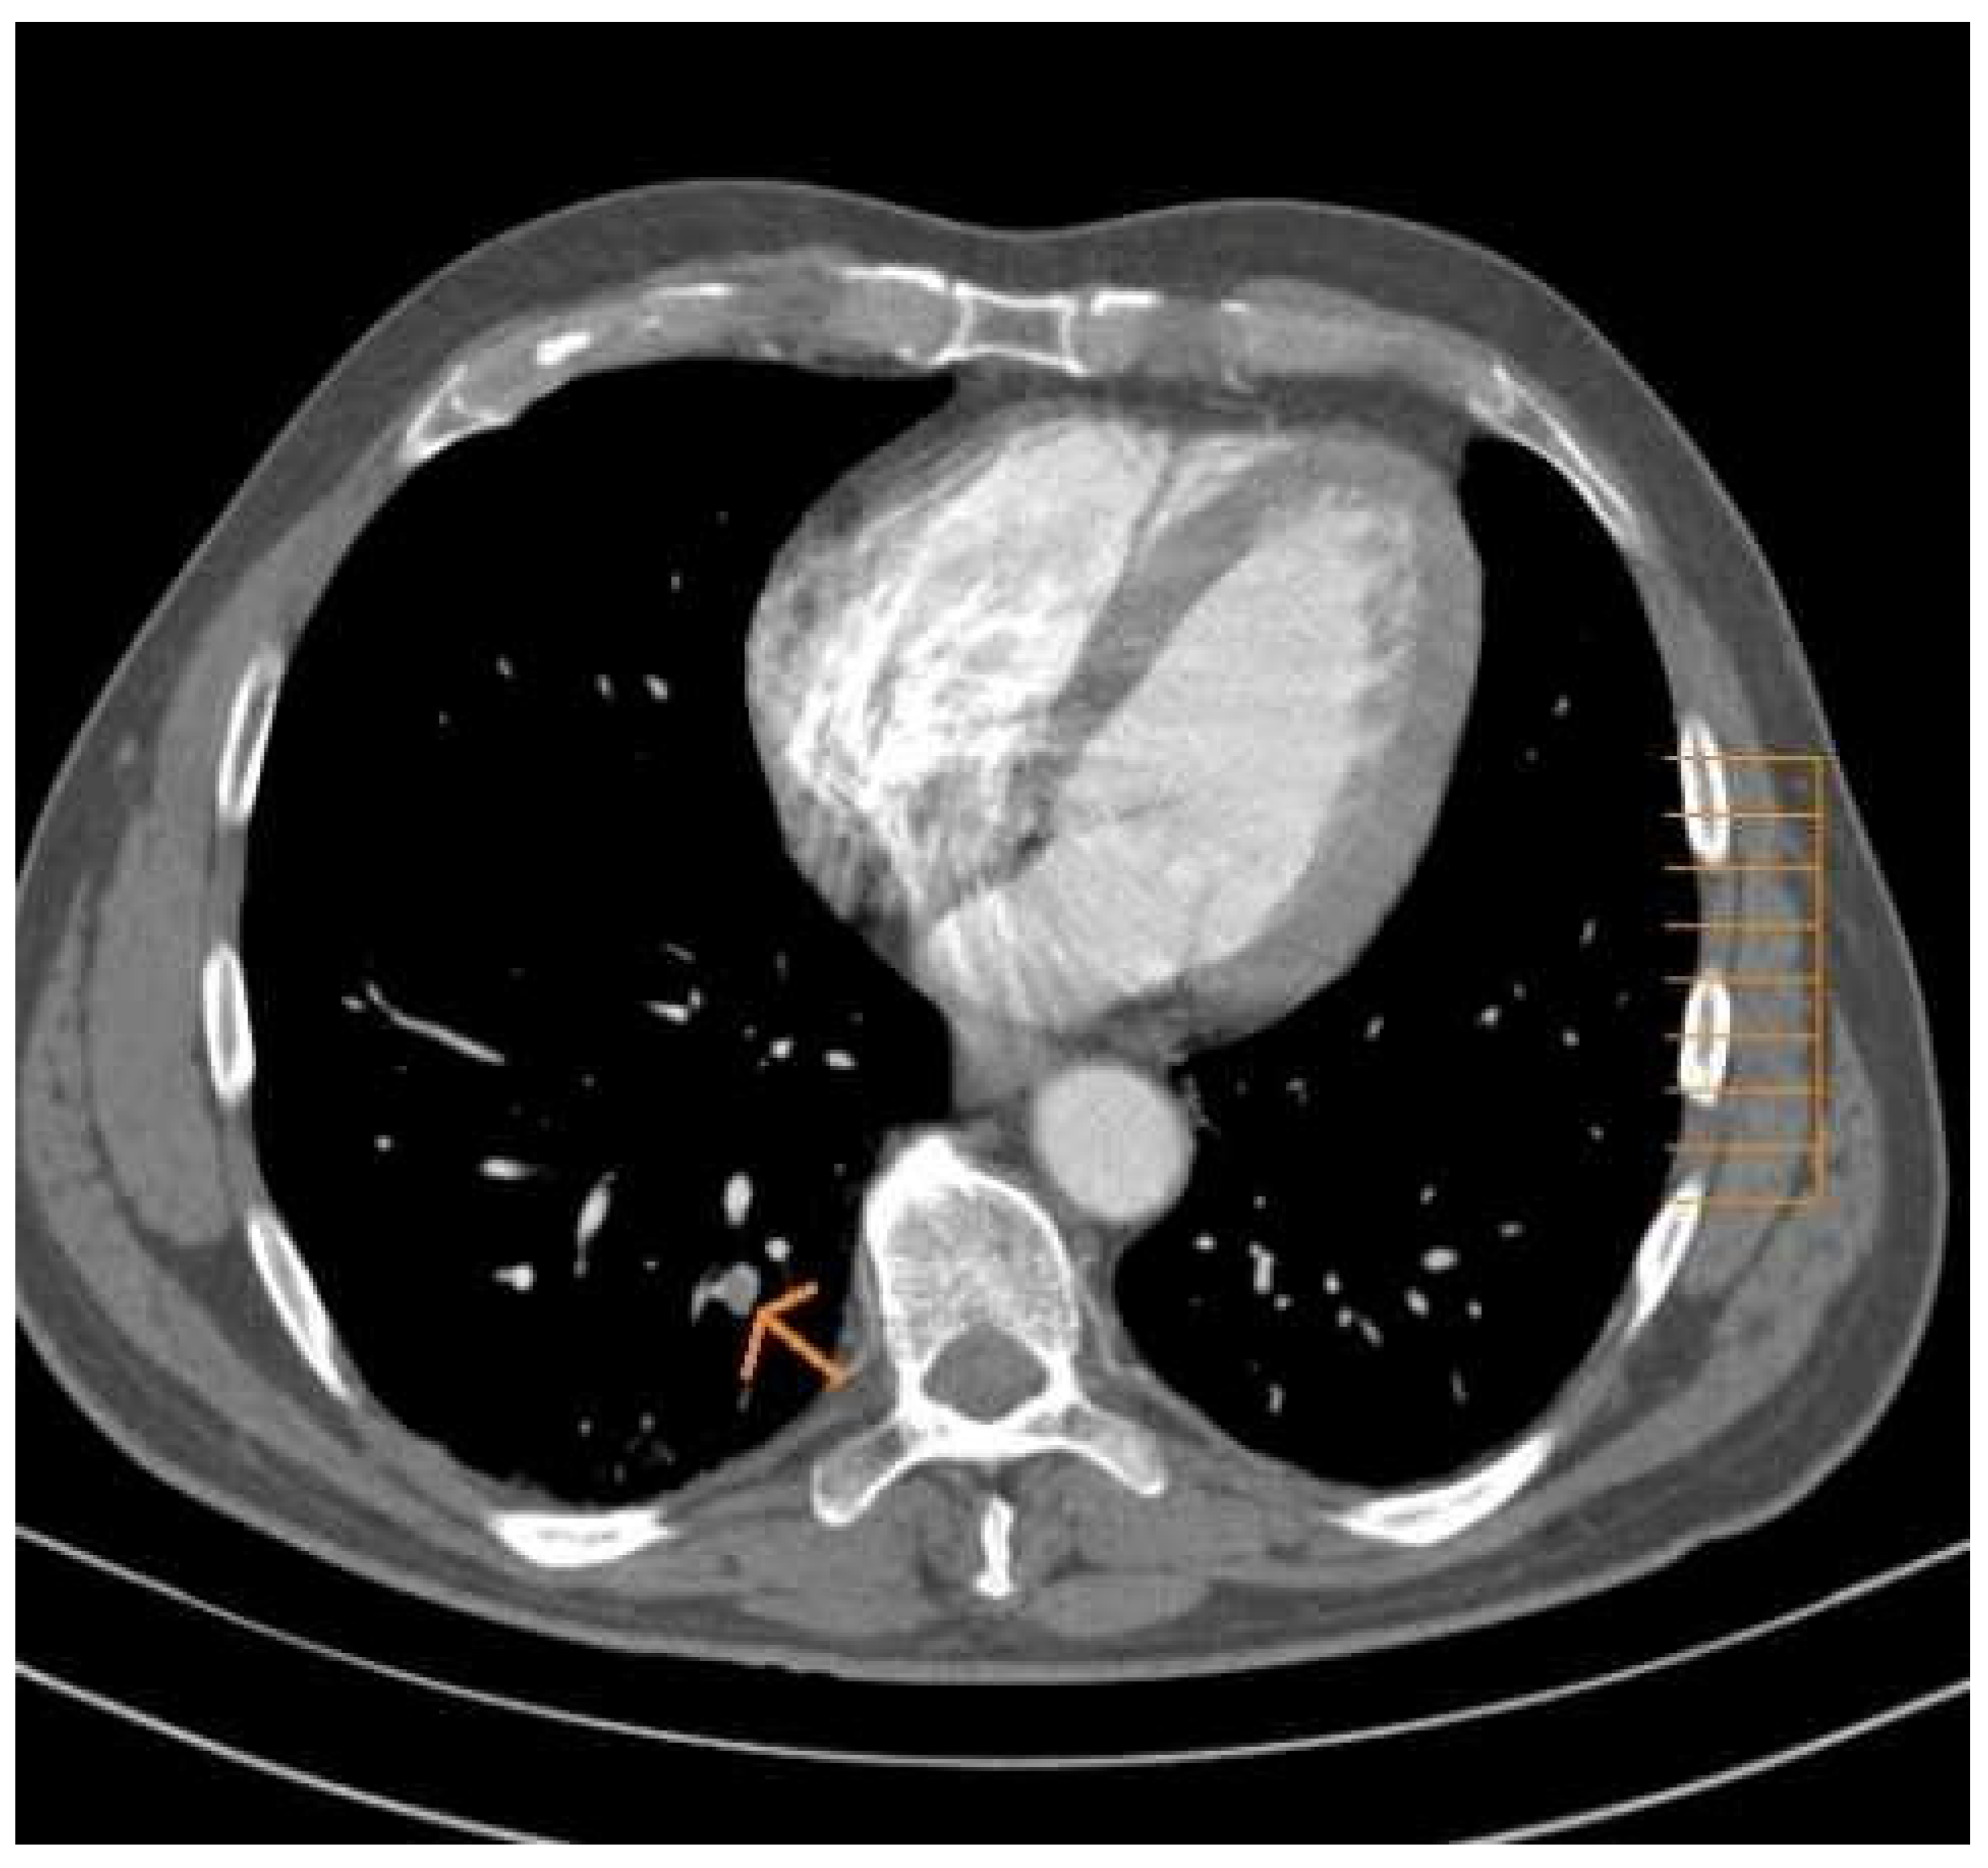

In another retrospective study involving 435 thoraco-abdomino-pelvic scans performed in a group of patients with cancer, pulmonary embolism was detected in 13 computed tomography (3.3%), While 6.8% of patients had asymptomatic iliofemoral DVT and 1.2% had common Iliac DVT (Figure 1). The association DVT / PE was more common in inpatients (p = 0.002, 0.004, relative risk [RR] = 1.6 / 2.1 respectively) and this was observed mainly in patients with a metastatic stage of their cancer pathology (23).

Figure 1. Asymptomatic subsegmental Pulmonary Embolism.